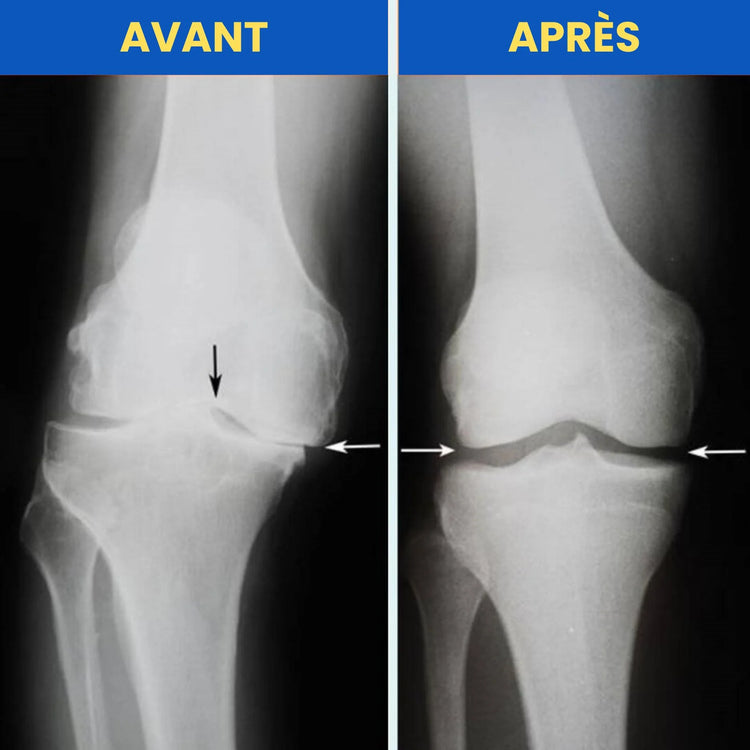

Avant

Après